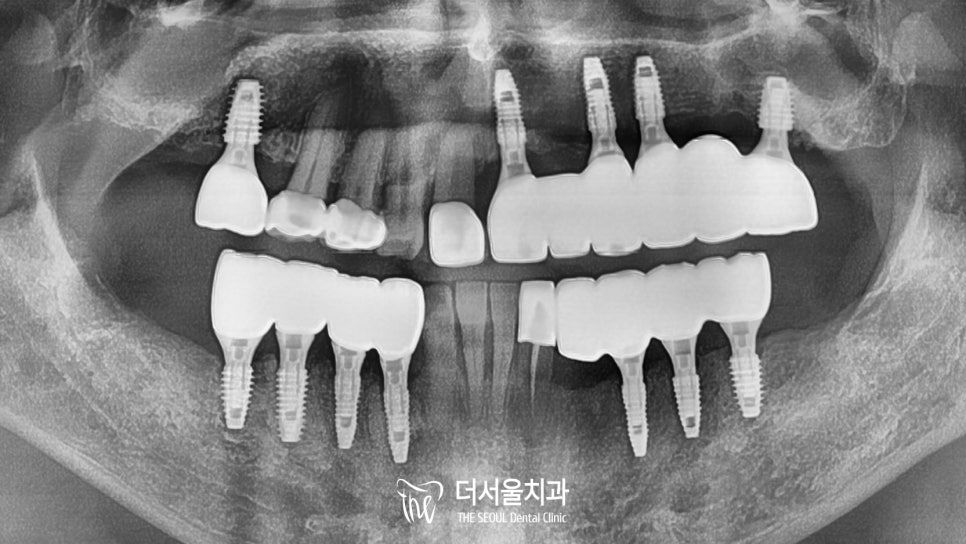

『자, 크라운이 올려져 있는

구강 내를 살펴볼까요?』

조직적으로나, 기능적으로나

흠잡을 곳이 없을 정도로

개선된 보철의 모습을 확인할 수 있습니다.

남아있는 자연치들과도

조화를 잘 이루고 있는 모습인데요.

임플란트 가운데에 뚫려 있는 홀은

최종 부착을 마친 후에

감쪽 같이 메꿔드릴 예정입니다!